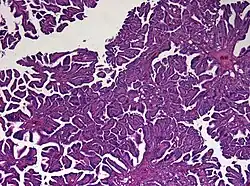

Histologie

Das feingewebliche Bild ähnelt mit Ausbildung papillärer Strukturen weitgehend dem des normalen Plexus choroideus. Tumoren, die atypische histologische Eigenschaften (insbesondere eine erhöhte mitotische Aktivität) aufweisen, werden als atypisches Plexuspapillom bezeichnet.[5]

Diagnostisch hilfreich ist der immunhistochemische Nachweis einer Expression des Zytokeratins CK7, Vimentin und S-100. Schwierigkeiten kann bei Erwachsenen die Abgrenzung gegenüber Hirnmetastasen bereiten. Der Nachweis einer Expression von plexustumor-spezifischen Markern kann dazu beitragen, die Verdachtsdiagnose eines Plexuspapilloms zu erhärten.[6][7]